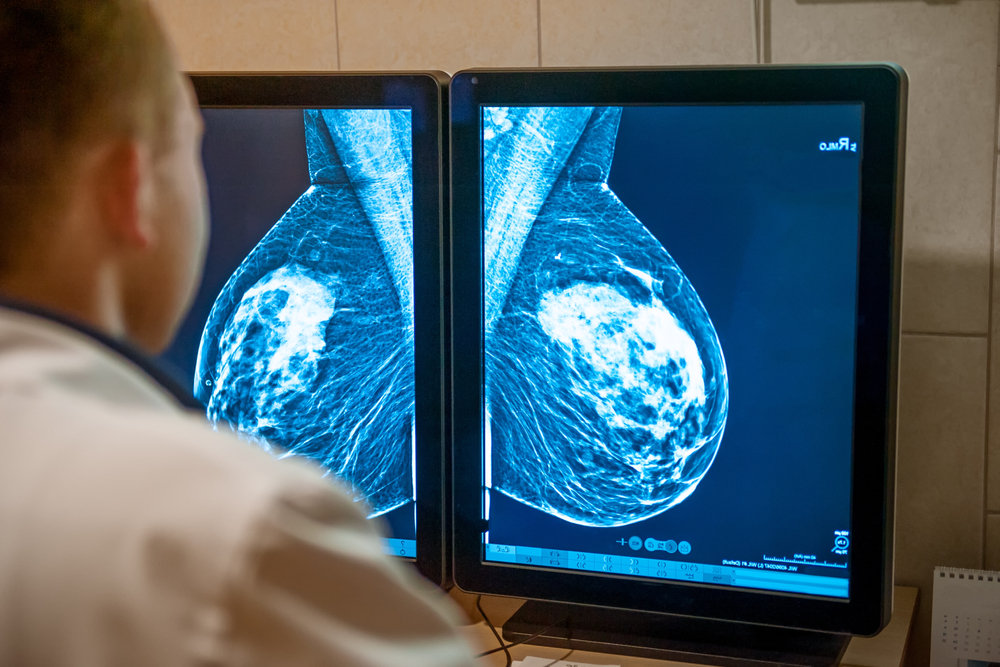

An image-only artificial intelligence (AI) model for predicting five-year breast cancer risk provided stronger and more accurate risk stratification than breast density assessment, according to a new study.

Clairity Breast is the first image-only AI breast cancer risk model cleared by the FDA and was trained on 421,499 mammograms from 27 sites in Europe, South America, and the United States.

By using mammograms from both women who developed cancer and women who did not develop cancer over the next five years, the AI model was able to learn patterns and differences in breast tissue that predict breast cancer risk.

Dr. Lehmann explained: “This model can detect changes in breast tissue that are invisible to the human eye, a task that radiologists cannot perform.”